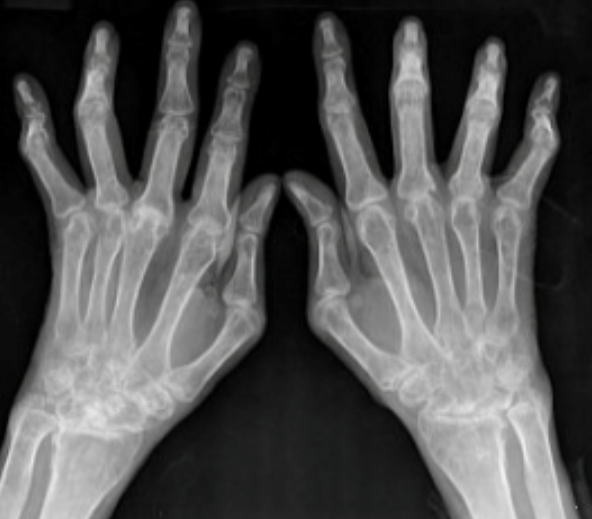

류마티스 관절염

손가락 저림이나 뻣뻣해지는 증상이라는 것은 건초염과 크게 다르지 않습니다.

다만 자가면역 질환 중 하나라는 것이 일반적으로 알려진 바인데요. 신체를 지켜주는 면역체계가 무너지면서 내 몸을 공격하게 되는 현상입니다.

특히 아침에 일어났을 때 손가락 관절로부터 다른 연골이나 뼈까지 통증이 이어지는 증상이라면 류마티스 관절염을 의심해봐야 합니다. 중년 여성들에게 높은 비중으로 나타나기는 하지만 연령대나 성별을 국한시켜서 볼 수는 없습니다.

류마티스 관절염의 경우 염증이 퍼지는 형태이기 때문에 의심이 되는 경우 빠르게 병원을 찾아 진료받는 것이 좋습니다.